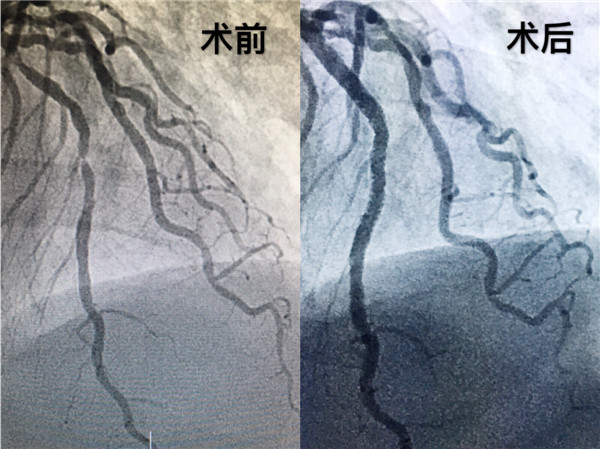

患者女性,63岁,一周前一次外出中感觉胸口闷,气短,并且伴有后背酸痛,自己服了速效救心丸症状缓解,没有引起重视,四天前受凉后症状加重,从阎良急转至我院,邓捷主任医师接诊后仔细观察患者心电图,评估病情,患者属于急症,患者及家属情绪焦灼难耐,邓主任考虑到患者病情及心理状态,决定放弃周末休息时间,带领手术团队为其行冠脉造影术。完善术前准备,造影示冠脉三支血管均存在病变,最严重处堵塞95%,立即为患者前降支植入支架两枚,考虑到患者安全,暂时撤台,转入心内重症监护室继续观察。四日后患者病情稳定,再次行造影术,为了更清晰探查血管内病变,置入OCT导管,术中示患者血管存在纤维斑块、脂质斑块、钙化斑块,血管内血流已是“一线天”的状态。俗话来讲,就好比水管里被沙石堵塞,水管内壁一圈附着了坚硬的水垢,水流艰难的通过一丝小缝隙,可见此患者胸闷、胸痛症状元凶在于此。要想恢复正常的血流,必须克服斑块带来的各种困难。医学圈内一句俗语说得好:“千不怕万不怕,就怕病变有钙化”。而OCT是评价钙化病变面积、深度和体积的金标准。

经过手术团队对图像缜密的研究,为患者右冠脉和左冠脉回旋支植入冠脉支架,血流恢复TIMI 3级,手术耗时一小时余。术后患者症状逐渐减轻,焦虑的情绪渐渐平复。至此,由邓捷主任带领的冠脉团队成功完成我院首例OCT指导下冠脉支架植入术。